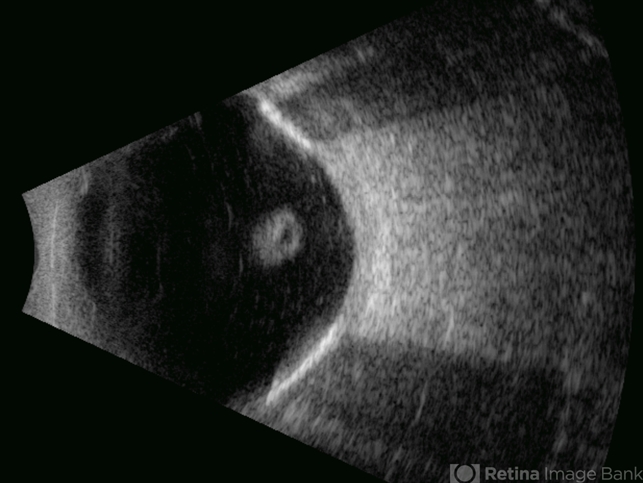

- open funnel RD, Retina detachment

- Gustavo U. Fonseca Aguirre, Hospital Conde de Valenciana, Ciudad de México

- Ultrasonography device

- This B-mode transverse ultrasound scan reveals a chronic rhegmatogenous retinal detachment, demonstrating a funnel-shaped configuration with a narrow intraluminal space. Two hyperechoic choroidal calcifications are present, indicative of chronicity.